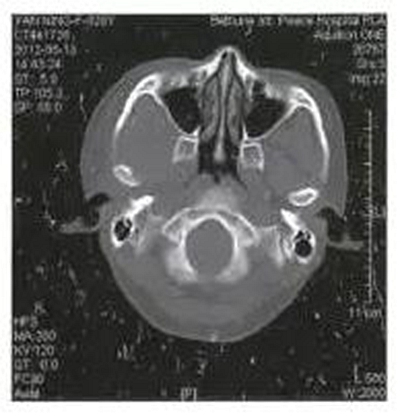

病例1,男,26歲。1月前在當?shù)劓?zhèn)醫(yī)院拔除左上頜第三磨牙,術(shù)后3天出現(xiàn)左側(cè)面部腫脹,疼痛,張口受限,張口度約20mm,在當?shù)剡M行全身抗生素治療,局部未予任何處理,效果不佳。CT示左側(cè)咬肌間隙及顳下間隙腫脹,左側(cè)髁突頸部骨質(zhì)破壞,明顯死骨形成(圖1)。

圖1左側(cè)髁突骨髓炎,死骨形成